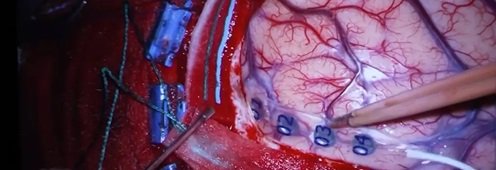

Belemtürk Haber Merkezi – Belçika’da beynimizin konuşma yeteneğini düzenleyen bölümdeki tümör ameliyatla alınırken, hastanın ameliyat esnasında konuşma yetisini kaybedip kaybetmediğini görmek için uyanık tutularak ameliyat ediliyordu.

Genk şehrindeki Oost-Limburg Hastanesi’nde ilk kez yeni bir teknik kullanan cerrahlar, hastayı uyandırmadan beynindeki tümörü almayı başardılar.

Beyin cerrahı Christophe Oosterbos, “Bu sayede ameliyat sırasında beyindeki konuşma merkezini doğru bir şekilde izleyebildik ve hastanın konuşmasını kaybetmediğinden emin olduk. Önceden bu ameliyat için hasta en az 5 saat uyanık kalmak zorunda kalıyor ve bu durum hasta için çok rahatsız edici oluyordu. Ülkemizde ilk defa elektrosensörlerle operasyonu başarıyla gerçekleştirdik.” sözlerine yer verdi.

Belçika’da daha önce hiç kullanılmayan bir teknikle, beyninde tenis topu büyüklüğünde tümör bulunan 44 yaşındaki hasta, uyutularak genel anestezi altında başarılı bir ameliyatla sağlığına kavuştu.